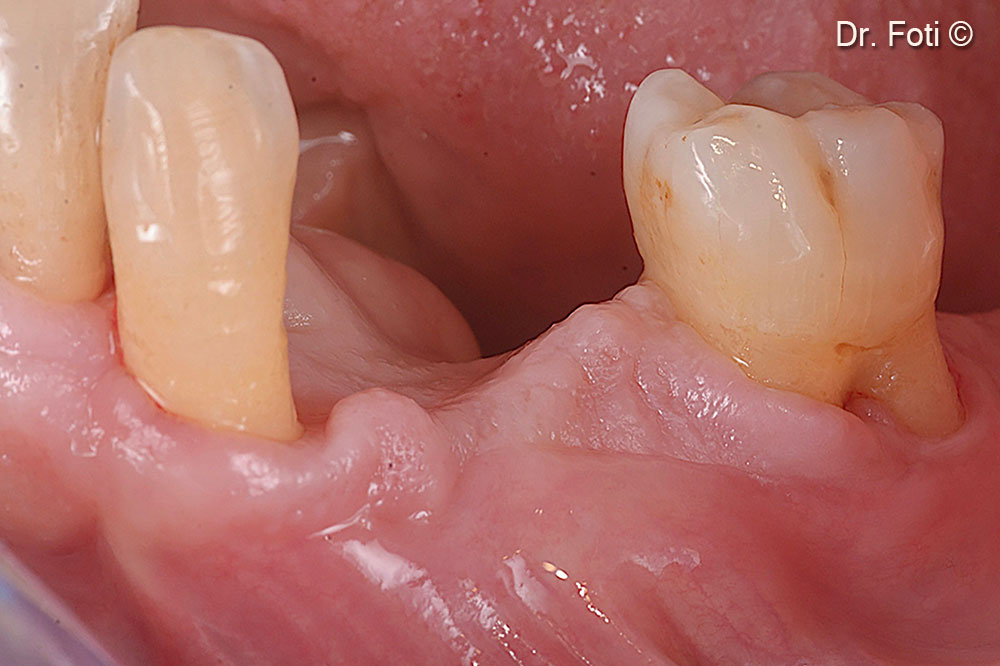

Since, compared to other techniques, there is no need to remove barriers, pins, or screws, a minimally invasive, partial-thickness incision is made to expose the implants.

Two healing abutments are placed six months after the surgery

5/0 monofilament sutures sling around the healing abutments.